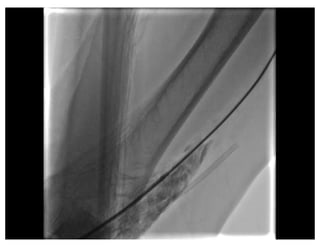

Balloon Assisted Tracking

Razor Effect

Patel T, et al CCI 2012

Razor Effect Balloon AssistedTracking Patel T, et al CCI 2012